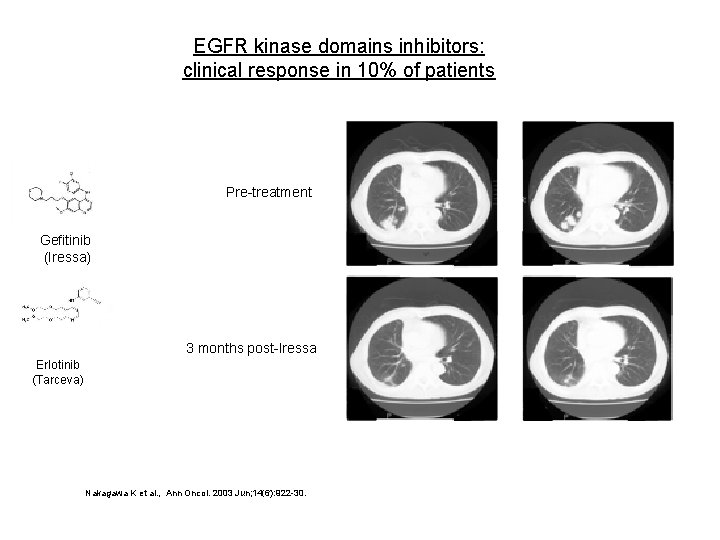

EGFR kinase domains inhibitors: clinical response in 10% of patients Pre-treatment Gefitinib (Iressa) 3 months post-Iressa Erlotinib (Tarceva) Nakagawa K et al. , Ann Oncol. 2003 Jun; 14(6): 922 -30.